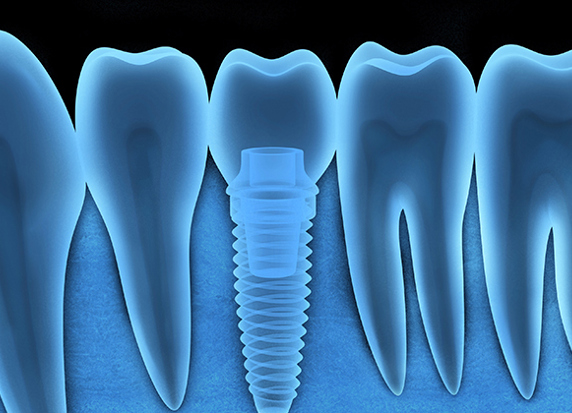

More InfoRoot Canal Therapy

Root Canal treatment can save a tooth from extraction and relieve pain caused by inflammation and infection